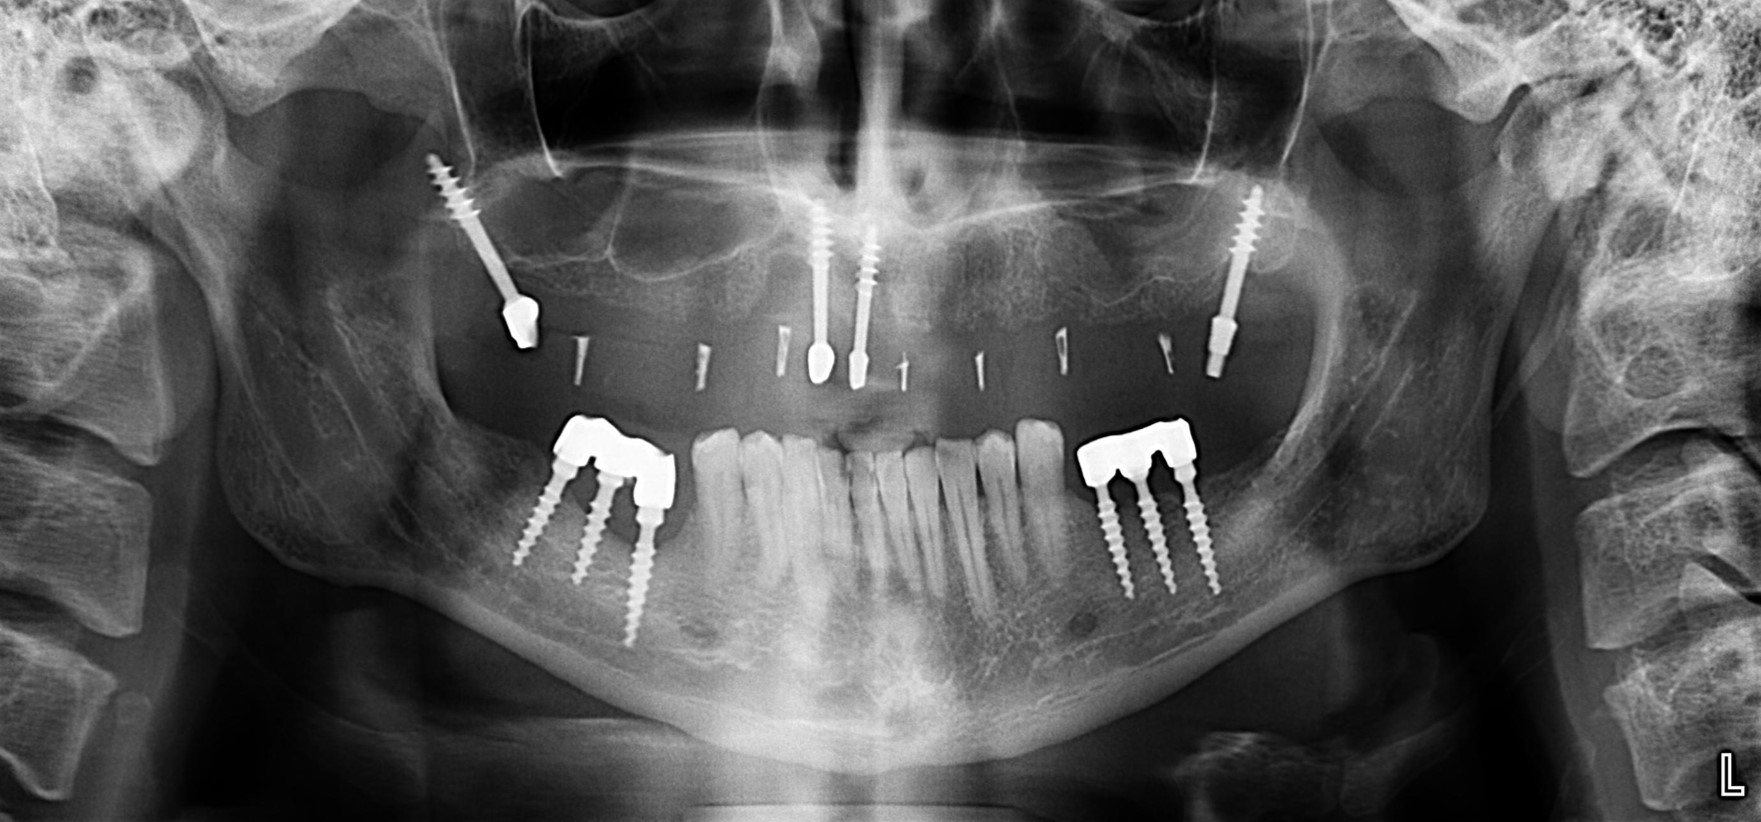

А теперь посмотрите снимок этого пациента:

Как вы считаете, что будет травматичнее и опаснее: установка шести имплантов такой формы или два простых синуслифтинга и шесть обычных имплантов?

Вот пациент, молодой парень, которому также успели удалить все зубы и наставить базальных имплантов:

из восьми верхних имплантов осталось четыре, мы их пока используем для стабилизации временного съемного протеза. На то время, пока проводим остеопластику и имплантацию в боковых участках.

Нижние, вроде как, вполне держатся, на них стоят постоянные металлокерамические коронки. Помните, что я говорил про один из главных критериев качественной имплантологической работы? Состояние десны вокруг имплантов!